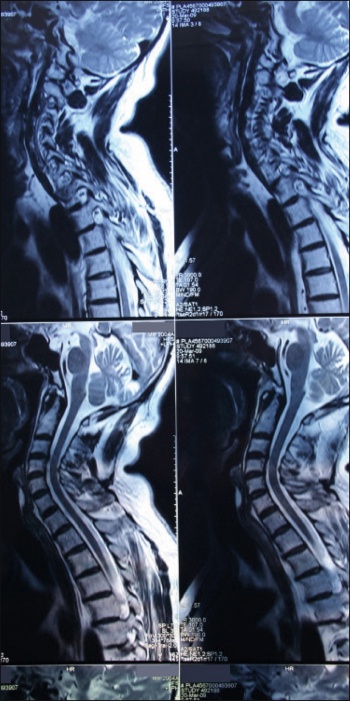

MRI is the most effective way of showing whether a patient’s back pain is amenable to minimally invasive surgery, according to neurosurgeon Mr Steven Young(click to enlarge)